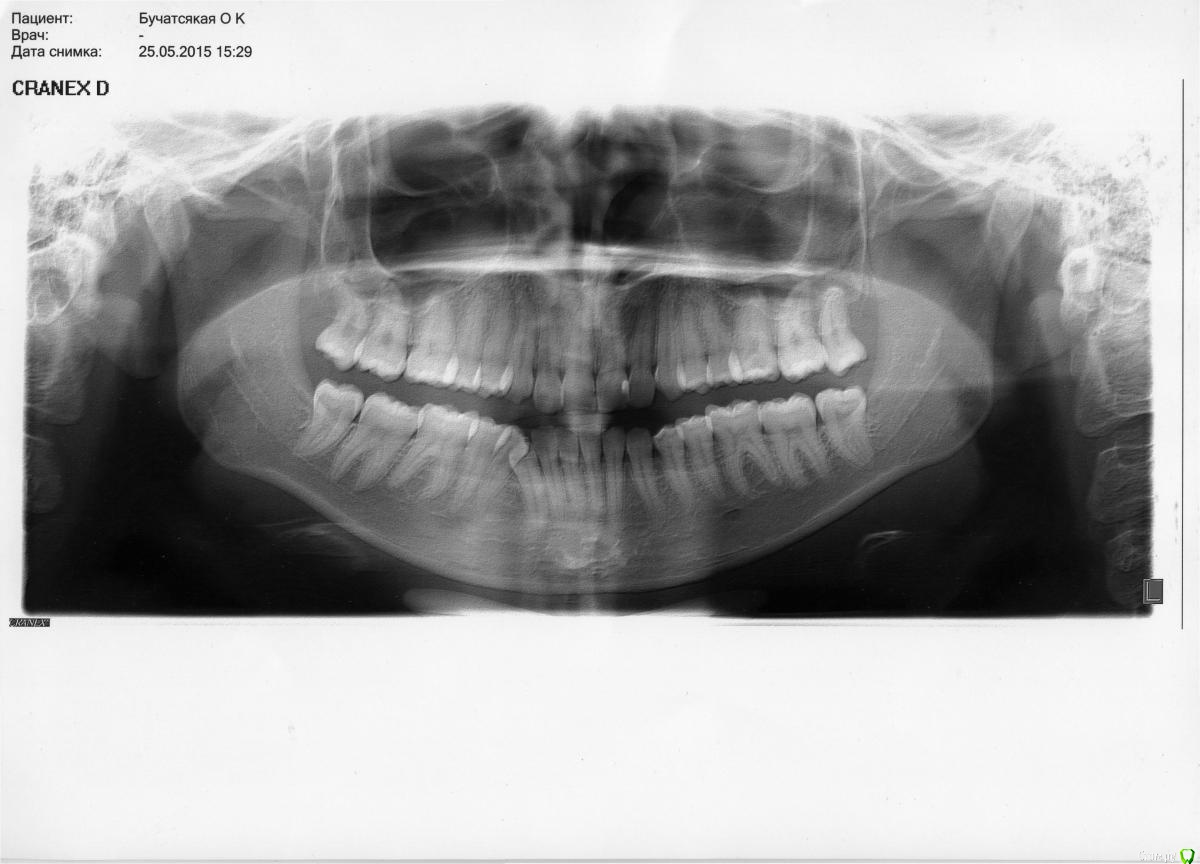

Opdihatop Опубликовано 10 декабря, 2016 Поделиться Опубликовано 10 декабря, 2016 Добрый вечер, коллеги! У меня вопрос к тем, у кого опыта по MEAW больше, чем у меня. Пациентка, 24 года, на данный момент все зубы мудрости удалены, привычная окклюзия по резцам - край в край. Сам процесс я понимаю, но есть несколько нюансов, которые хотелось бы уточнить:1) Нивелировать ли просто фронт в/ч, как книжка пишет (просто поставить дугу и все), или все-таки немного дистализировать боковые участки? С одной стороны простое нивелирование ускорит процесс и облегчит перебрасывание резцов, с другой стороны я опасаюсь чрезмерной протрузии из-за выравнивания дистопированных клыков; но при этом дистализация усугубит 3-й класс.2)Какой высоты делать окклюзионные накладки, в книжке они минимальные, а мне как то хочется побольше, чтобы резцы разомкнуть почти край в край, но не испортит ли это биомеханику?Буду очень благодарен вам за помощь! Ссылка на комментарий